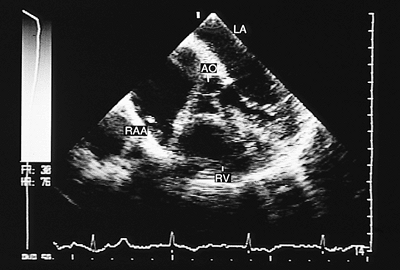

Congenitally Corrected Transposition

In congenitally corrected transposition, both the A–V and the V–A connections are discordant. Associated defects, especially ventricular septal defect, either isolated or with pulmonary valve stenosis, are common, occurring in 70% to 90% of cases. Cardiac malpositions also are commonly associated and can make it difficult to obtain satisfactory transthoracic recordings. The study of these patients should include transesophageal and transgastric recordings, and the main findings are discussed in the following paragraphs (4).

A–V discordance is established by identifying atrial situs and the position of the ventricles using the criteria discussed at the beginning of the chapter. The most reliable way of identifying the atria is through the morphology of the atrial appendages. The principal signs used for the identification of the ventricles are the different levels of implantation of the mitral and tricuspid septal leaflets (when ventricular septal defect is absent) and insertion of the tricuspid chordae tendineae in the interventricular septum. In addition, the ventricular morphology evident in the four-chamber image facilitates recognition—the right ventricular chamber has a triangular shape and the left ventricular chamber an ellipsoid form. These characteristics are independent of the ventricular spatial relationship.

In V–A discordance, identification of the great arteries is based on the bifurcation of the pulmonary artery. The parallel positions of the two vessels can be observed with monoplanar recordings taken at the level of the semilunar valves. When situs is solitus, the aorta is anterior and to the left and the main pulmonary artery posterior and to the right (Fig. 8.2.48). In situs inversus the aorta is anterior but to the right of the main pulmonary artery.

Direct visualization of the connection of the ventricles to the great vessels is facilitated by the use of biplanar transducers. In images in the longitudinal plane it is possible to visualize the connection of the posterior vessel (pulmonary artery) with the left ventricle, to corroborate mitral-pulmonary continuity and to demonstrate the connection between the anterior outflow tract (right ventricular) and the aorta.

It is possible to identify cardiac position from the transesophageal four-chamber image. The apex of the ventricles points to the left in levocardia, to the right in dextrocardia, and toward the midline in mesocardia. Moreover, the subpulmonary outflow tract of the left ventricle is deeply wedged between the mitral and tricuspid valves, which generates malalignment of the atrial and ventricular septum and prominent anterior recess in the morphologically left ventricle.

Transesophageal study is superior to the transthoracic study for visualizing the frequently associated ventricular septal defect. The defect is usually a wide perimembranous type in subpulmonary position. It can be visualized directly in transverse or longitudinal planes.